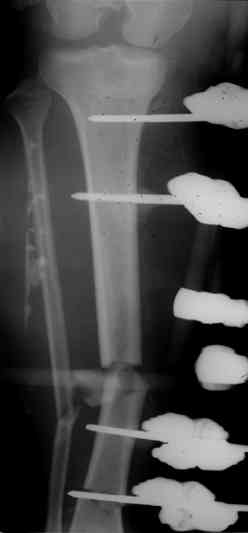

Коллеги! Прошу совета, какую тактику избрать при лечении.Больной 27 лет, мотоциклист. Поступил 23.04.10 ДЗ. О. перелом н.з левого бедра Gustillo 3b (c повреждение бедренной вены), О.Правого бедра Gustillo 2, з. фрагментарный перелом левой голени.При поступлении Hb 66 ISS 40, Фиксация стержневыми аппратами, сосудистые хирурги выполнили шов вены. Выполена резекция бедренной кости 9 см. На 7 сутки Желудочно-кмшечное кроветечение из стрессовых язв, 12 сутки флотирующий тромтоз 14 см установлен кава-фильтр. На 15 сутки закрытие ран местными тканями. Раны заживают первично. Воспаления на стержнях нет. В настоящий момент планируем. Переход со стержневых аппаратов на стержни с антибактериальным покрытием на правом бедре и левой голени. Левое бедро планируем продолжить фиксировать в стержневом аппарате.

Вопрос: что делать с левым бедром? Учитывая внутрисутавной характер перелома, дефект бедра 9 см.

На левом бедре оставили аппарат бедро-голень.

Как вы думаете если сделать следующее.

После заживления раны на левом бедре. Выполнить открытую реподицию и синтез пластиной для дистального бедра. Пластину в проксимальном направлении зафиксировать монокортикально.

А затем выпонить остеотомию бедра в верхней трети.

И тракцию бедра на стержне. Типа (СМ картинки).

После выращивания регенерата стержень блокировать.